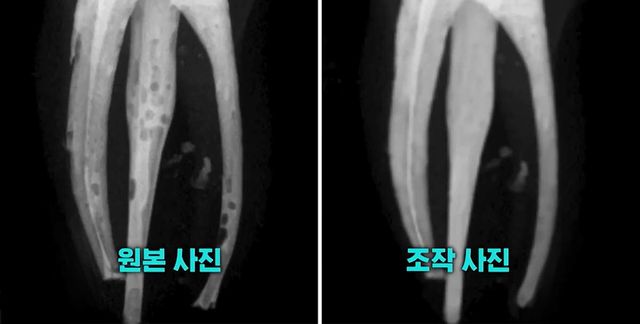

연세대 치과대학 본과 4학년생의 조작 사진. / SBS

원본 엑스레이 사진에는 신경치료 과정에서 충전재를 꼼꼼히 채워 넣지 않아 기포가 들어찬 모습이 여러 군데 보였다. 그러나 학생들이 교수진에 최종 제출한 사진은 기포 하나 없이 깨끗하게 치료된 모습이었다.